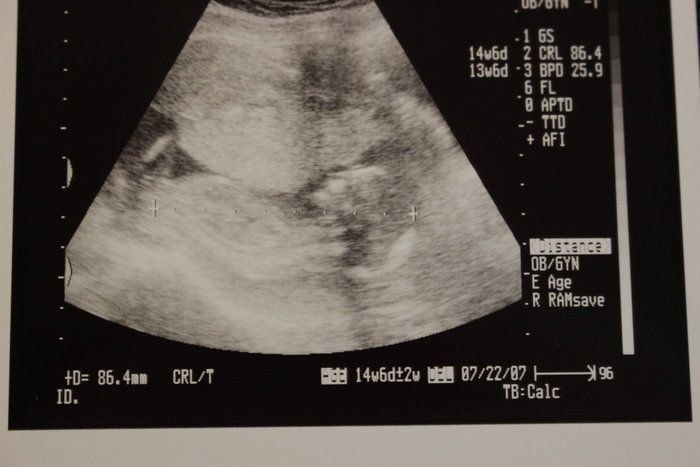

チャーミー小結さんの妊娠14週目のエコー写真

なんと人の顔らしきものと背骨が見えます。「ぽん太」という愛嬌あるネーミングにそぐわない端正な顔立ち・・・と早くも親バカを楽しみ始めた頃です。つわりと一日中襲ってくる眠気との闘いを支えるモチベーションになっていました。